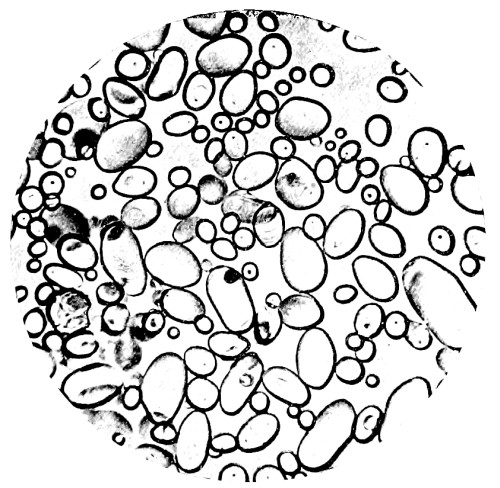

10. Photo-micrograph of Red Blood Corpuscles from Domestic Fowl 99

11. Photo-micrograph of Blood Corpuscles of Fish 99

12. Photo-micrograph of Blood Corpuscles from a Dried Stain of the Blood of a Cod-fish 100

13. Photo-micrograph of a Frog‘s Blood showing oval nucleated Red Corpuscles 101